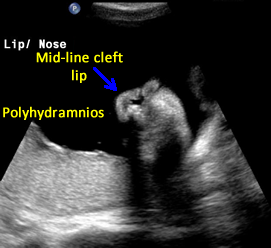

Above. Pentalogy of Cantrell. Case 1. 34 6/7 weeks gestation. Pentalogy of Cantrell showing cleft lip, another mid-line defect.

Above. Pentalogy of Cantrell. Case 1. 34 6/7 weeks gestation. Pentalogy of Cantrell showing sagittal view of fetal profile with the possibility of frontal bossing. Note the large mid-line cleft.